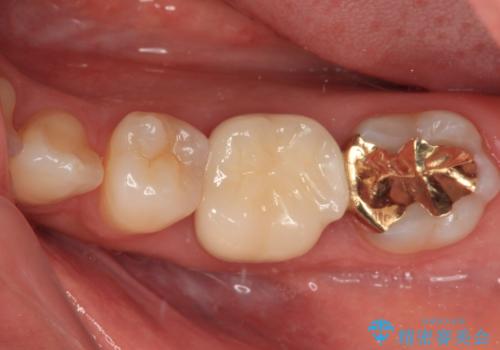

- 前歯のすきっ歯を気にして来院された患者様です。

矯正かオールセラミックか、治療の選択がありましたが、ご年齢や色の濃い点を考慮してオールセラミッククラウンにて補綴することとしました。

折角なのできれいに仕上げたいとのことで、オーダーメイドタイプのクラウンを選択されました。色調を周りのご自身の歯と合わせることができるため、自然な仕上がりをご希望の方におすすめです。